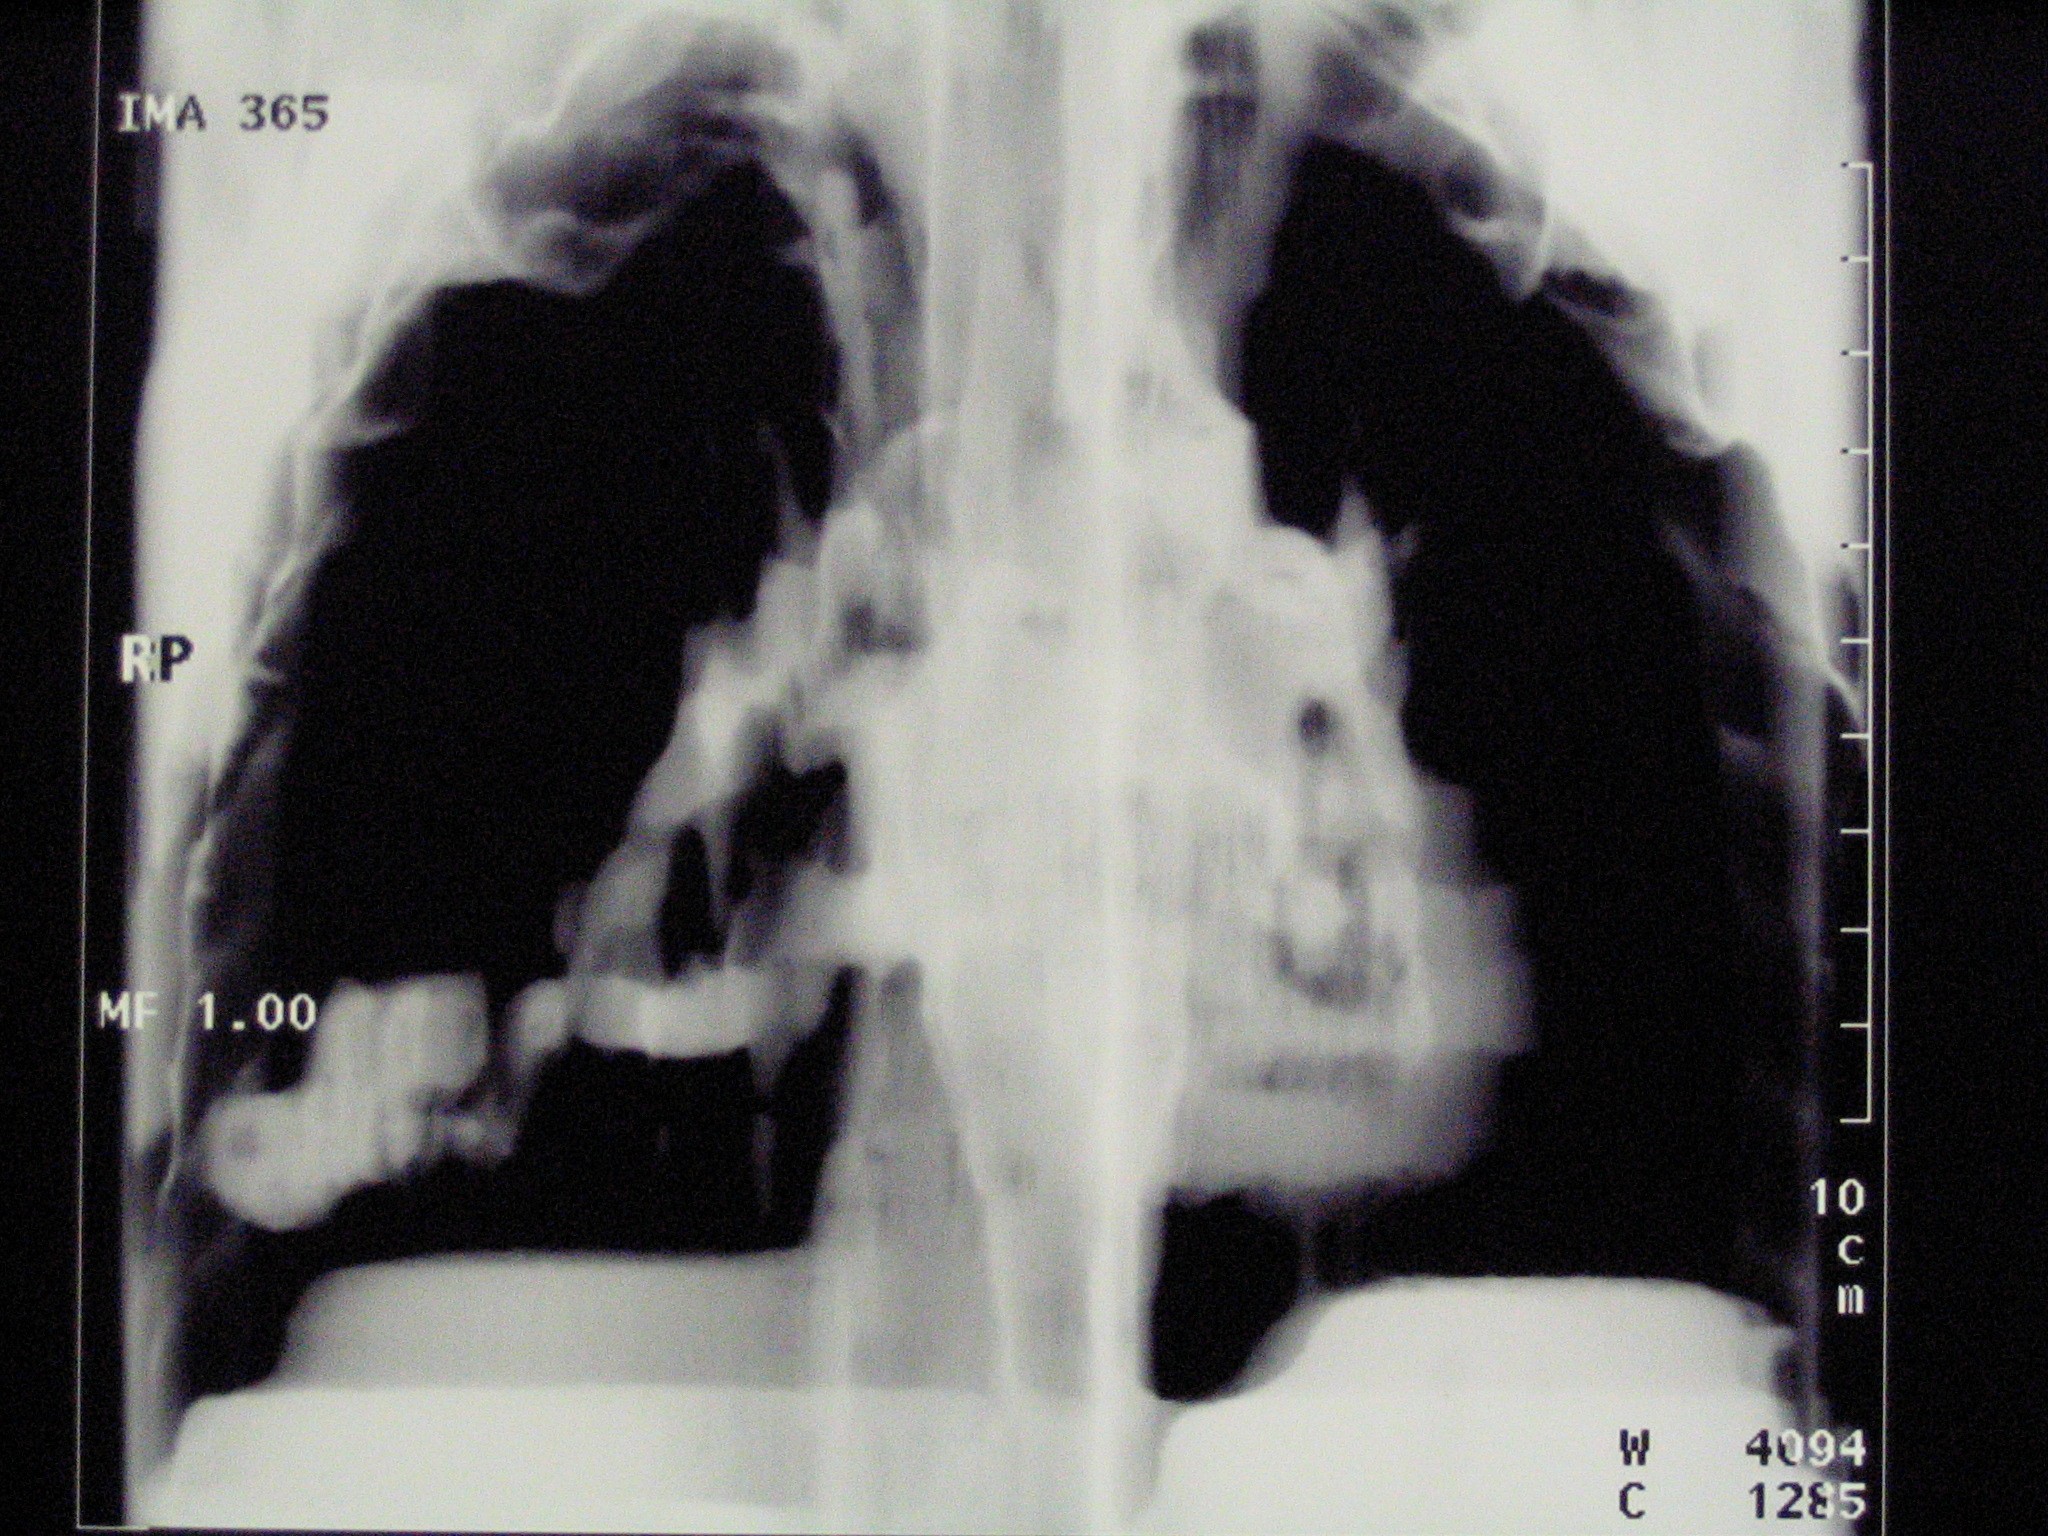

F. mostra all'esame obiettivo buone condizioni generali, cianosi periorale e alle estremit�; lingua e mucosa orale lievemente cianotiche. Dita a bacchetta di tamburo. Piccola teleangectasia al naso, numerosi spider naevi al volto, mani e avambracci, vermiglio labiale; fini teleangectasie non a chiazze alle regioni zigomatiche. All'apparato cardiaco: toni validi, ritmici, lieve impurit� sistolica. All'apparato respiratorio murmure vescicolare presente su tutto l'ambito polmonare. Addome trattabile, non dolente, organi ipocondriaci in limiti. Pressione arteriosa in range (100/75 mmHg). La saturazione dell'ossigeno in aria ambiente risulta, invece, gravemente ridotta (86-87%) sia in clinostatismo che in ortostatismo. Il quadro clinico, la policitemia, la ridotta saturazione dell'ossigeno considerati alla luce del dato anamnestico della malattia di Rendu-Osler-Weber nella mamma, ci hanno indotti a sospettare la presenza di una malformazione vascolare polmonare, compatibile con la malattia. Abbiamo pertanto effettuato una tomografia computerizzata del torace (TC) che ha evidenziato, a carico del parenchima polmonare di destra, la presenza di una grossolana anomalia vascolare a prevalenza venosa (vedi Figura a lato).

Per escludere la presenza di analoghe malformazioni vascolari in altri distretti, sono state effettuate inoltre una TC addominale e cerebrale, risultate entrambe nella norma. La bambina � stata sottoposta a embolizzazione percutanea della malformazione polmonare artero-venosa (MAV) con esito positivo. Nel post-operatorio si � assistito a graduale scomparsa della cianosi e della astenia sotto-sforzo. In base alla caratteristiche clinico-anamnesitche � stata posta diagnosi di malattia di Rendu-Osler-Weber. � attualmente in corso l'indagine molecolare.